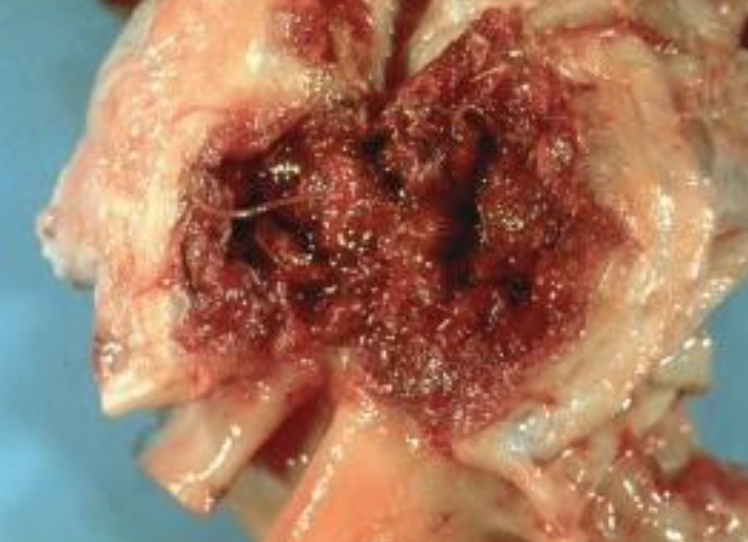

Which parasite caused this damage to the mesenteric artery?

Strongylus vulgaris